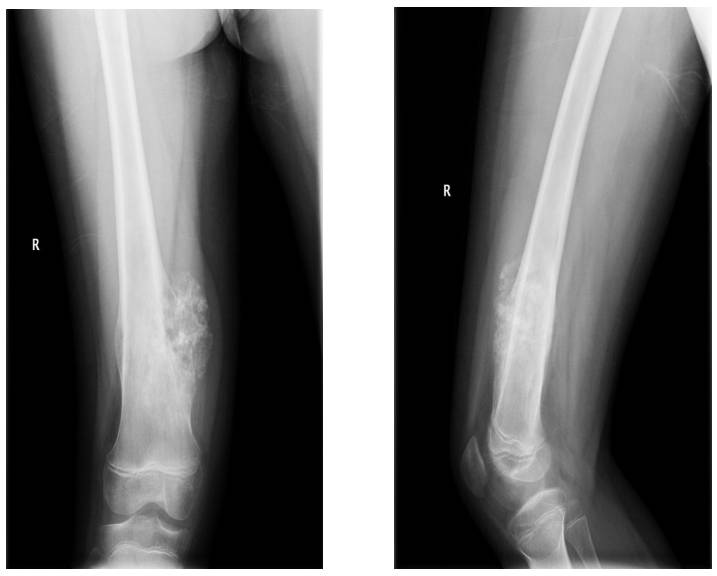

Ameliyat Öncesi: Röntgende distal femur medial yerleşimli kemikte harabiyete neden olan düzensiz sınırlı tümör kitlesi görülmekte